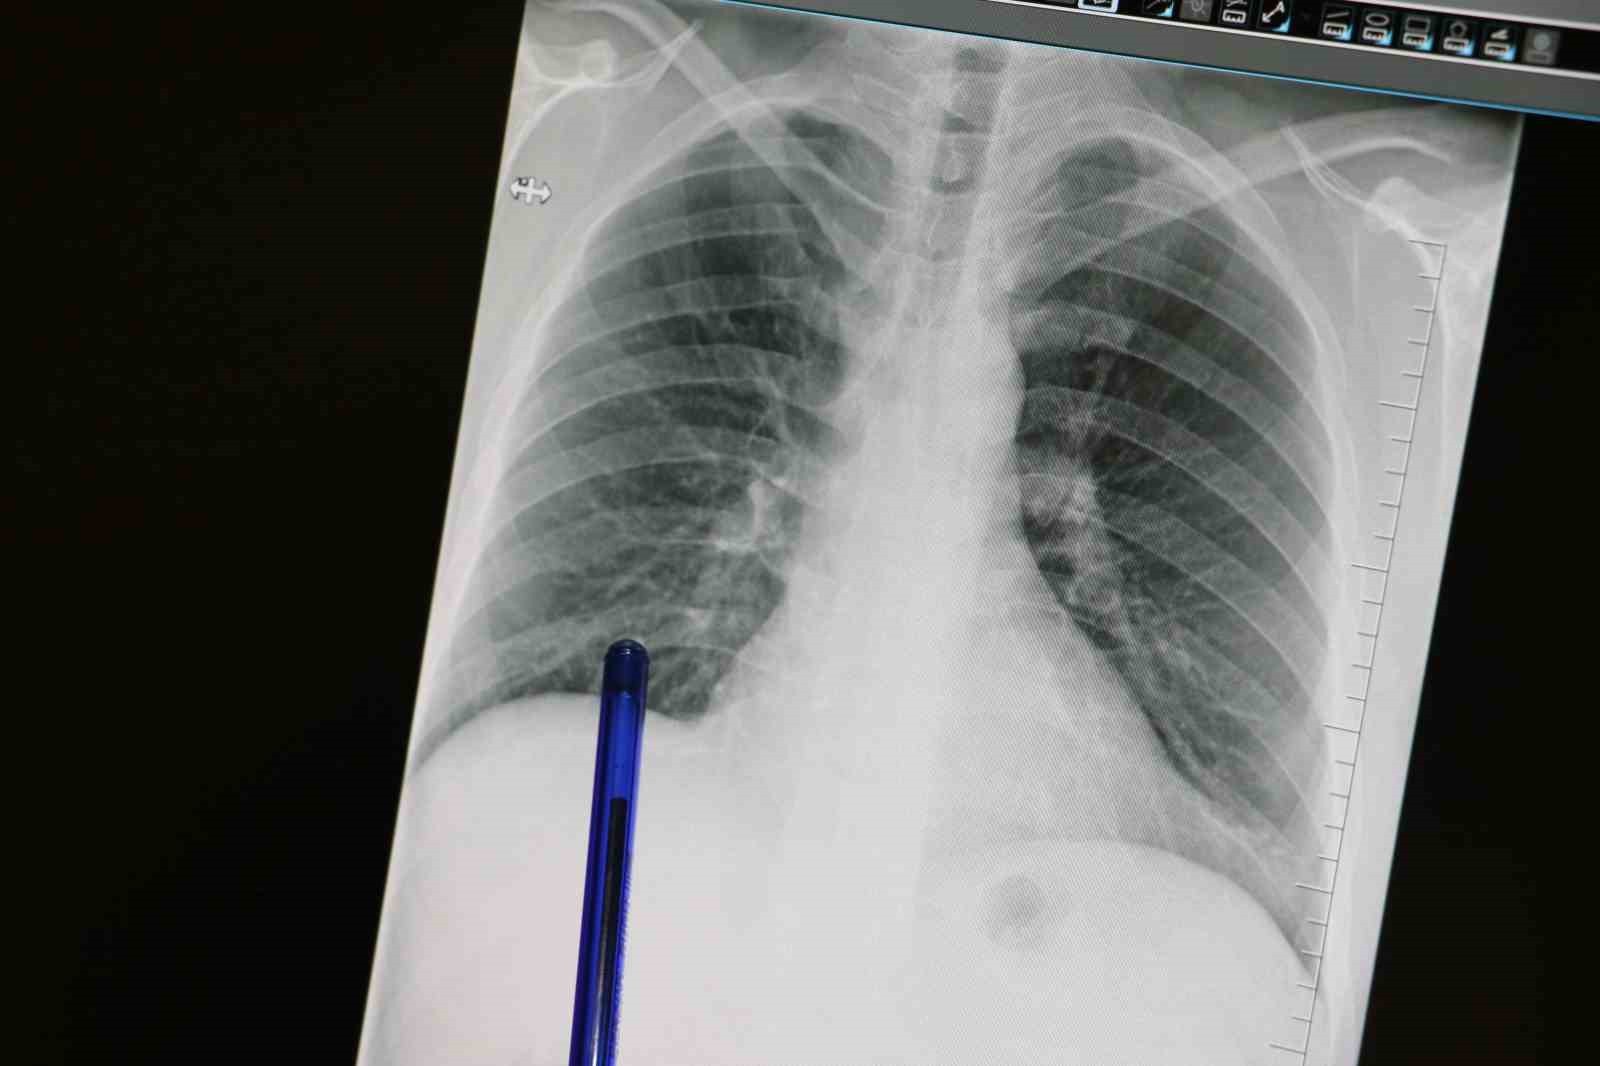

Basit Semptomlar Kanseri İşaret Edebiliyor

Göğüs Hastalıkları Uzmanı Dr. Büşra Yayla Yerlikaya, öksürük ve balgamın akciğer kanseri belirtisi olabileceğini vurguladı.

Medicana Sivas Hastanesi’nden Göğüs Hastalıkları Uzmanı Dr. Büşra Yayla Yerlikaya, akciğer kanserine dikkat çekerek, öksürük ve balgam gibi basit görünen belirtilerin bu ciddi hastalığın habercisi olabileceğini ifade etti.

Erken Tanı Hayat Kurtarıyor

Dikkat Edilmesi Gereken Belirtiler

Özellikle sigara içen bireylerin öksürük gibi belirtiler göstermesi durumunda bir uzmanla görüşmesi gerektiğini belirten Dr. Yerlikaya, "Akciğer kanserinin en yaygın belirtileri arasında uzun süren öksürük, balgamda kan, nefes darlığı, kilo kaybı ve göğüs ağrısı bulunmaktadır. Yeni başlayan veya karakter değiştirerek devam eden öksürük, acil bir değerlendirme gerektirmektedir," dedi. Erken tanının hayat kurtardığını vurgulayan Yerlikaya, 50 yaş üstü ve uzun süre sigara içmiş bireylerin düşük doz tomografi ile tarama yaptırma gerekliliğini belirtti.